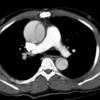

Ao Diss 1a

Date: 01/21/2006

Views: 4070